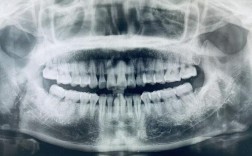

牙齿正畸是常见的口腔治疗方式,通过矫正装置调整牙齿排列和颌骨关系,改善咬合功能与面部美观,在正畸治疗前,全面的口腔检查必不可少,其中X光检查是评估口腔内部情况的关键手段,当女性处于怀孕这一特殊生理阶段时,牙齿正畸与X光检查的关联便需要格外谨...